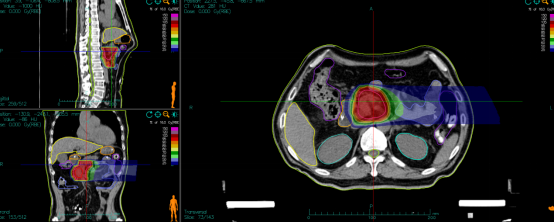

病例展示三:胰腺癌

腺癌病灶压迫并侵润十二指肠,十二指肠梗阻不能正常进食,患者留置营养管及胃肠减压管;伴胆道梗阻诱发黄疸,留置PTCD引流管。诊断:1.胰头恶性肿瘤 cT4N0M0 III期 KPS评分:80分;2.十二指肠不全梗阻;3.梗阻性黄疸,4.心律失常 室性期前收缩5. 慢性心力衰竭6.陈旧性心肌梗死7.冠状动脉粥样硬化性心脏病8. 缺血性心肌病。治疗:2024-05月开始吉西他滨+白蛋白紫杉醇化疗4周期,碳离子放疗剂量:PTV 36Gy(RBE)/9fx,后缩野补量,剂量:PTV boost 18Gy(RBE)/4fx,4.5Gy(RBE)/fx。

疗效评价